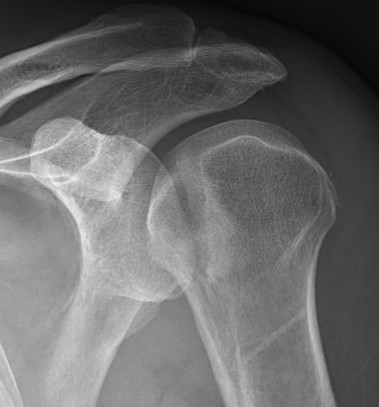

Scapular lateral

Center of the humeral head must be centered on the Y / Mercedes sign

Y is formed by

- coracoid anteriorly

- scapular spine posteriorly

- scapula body inferiorly

Posterior shoulder dislocation

Posterior shoulder dislocations